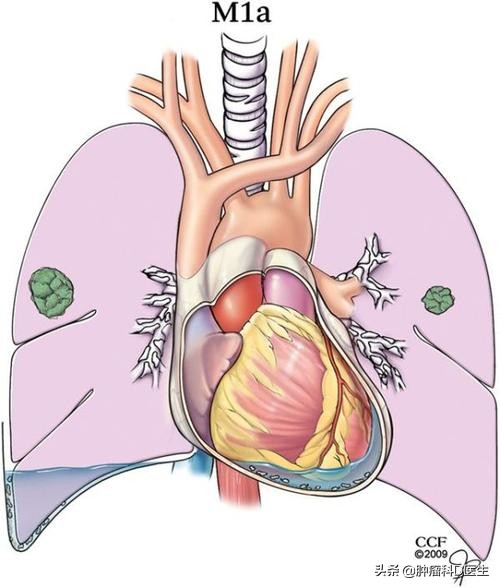

影响肿瘤分期:根据肿瘤TNM分期,出现恶性胸腔积液的患者诊断为M1,也就是常说的IV期肺癌;有人说我把胸水抽干净了,是不是就不是IV期了哪?本质上,出现胸水意味着胸膜出现了播散转移,胸膜上的小结节不会跟着胸水被放出来,所以仍然要诊断IV期肺癌。随后的治疗根据IV期肺癌的标准进行。

恶性胸腔积液为IV期肺癌